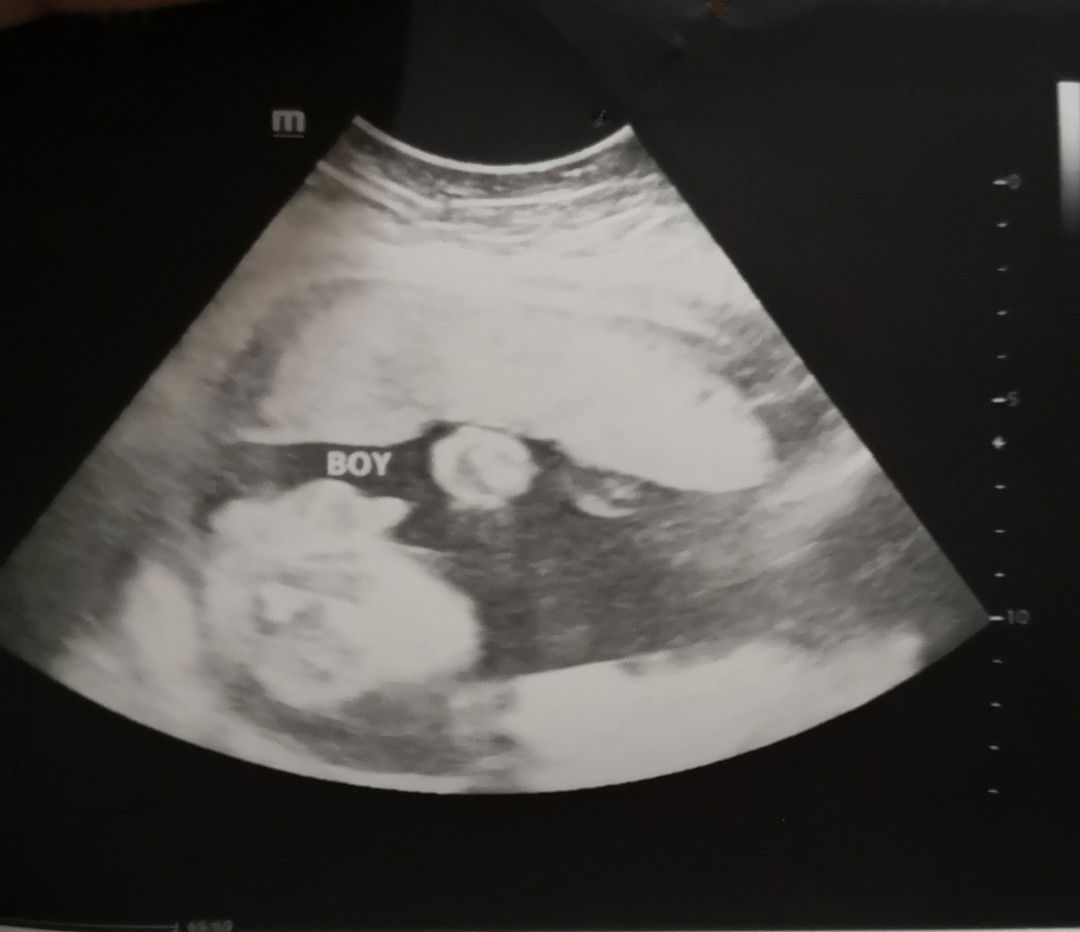

is it really a boy?

Hello everyone! mga mommies need your opinion, first time mom po 26 weeks pregnant, nagpa ultrasound po ako to see my baby's gender sabi ng ob its a boy daw but she never explained pano nya nasabi. curious lang po pano sya nalalaman? and if boy po ba talaga si baby? thanks all :)